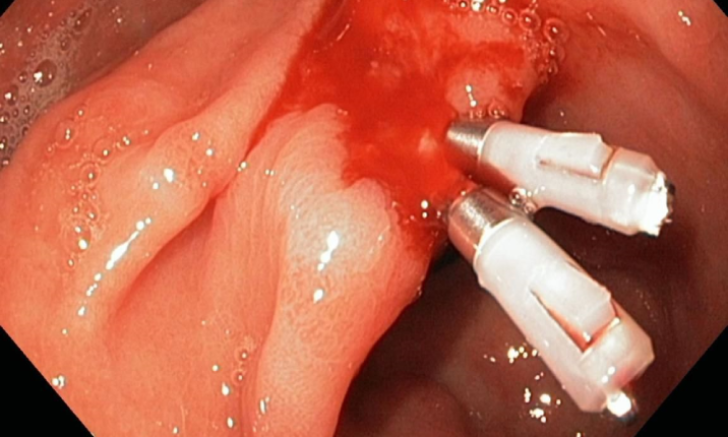

- Hemostasis